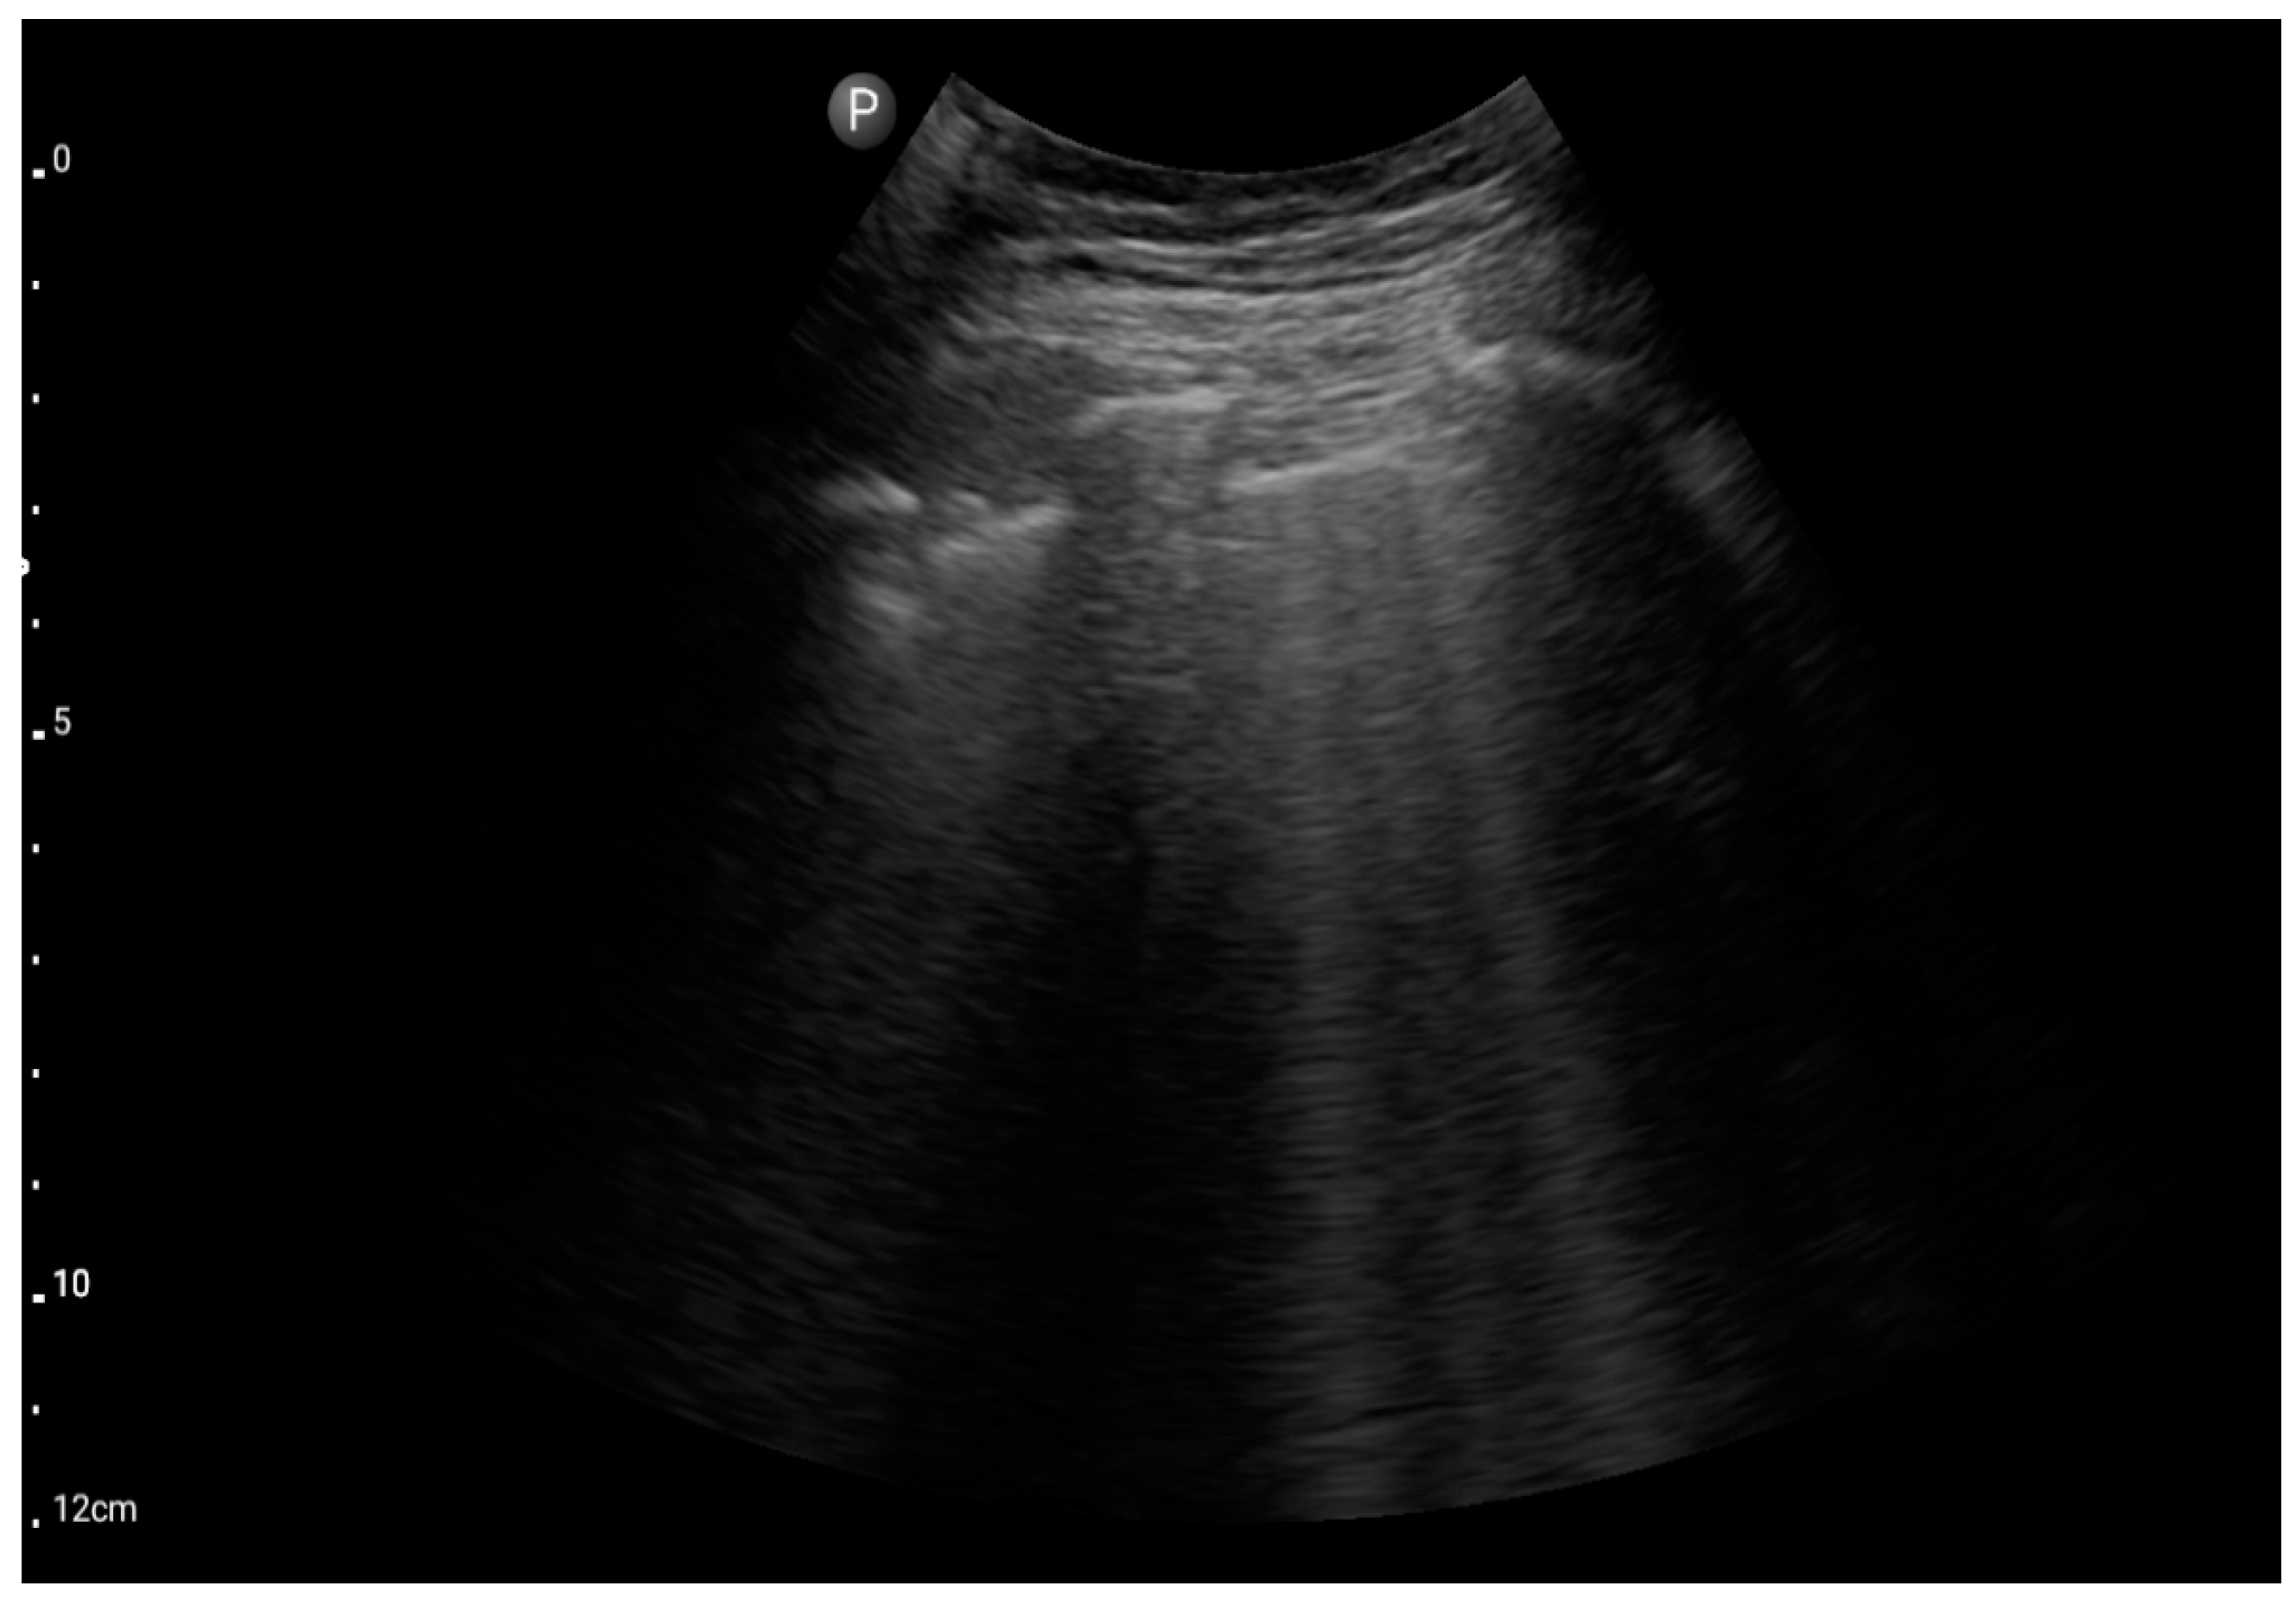

Figure 5.

Convex probe; view: lungs, two intercostal spaces-“Merlin space” with B-profile (BLUE protocol), (source: author’s material—DK).